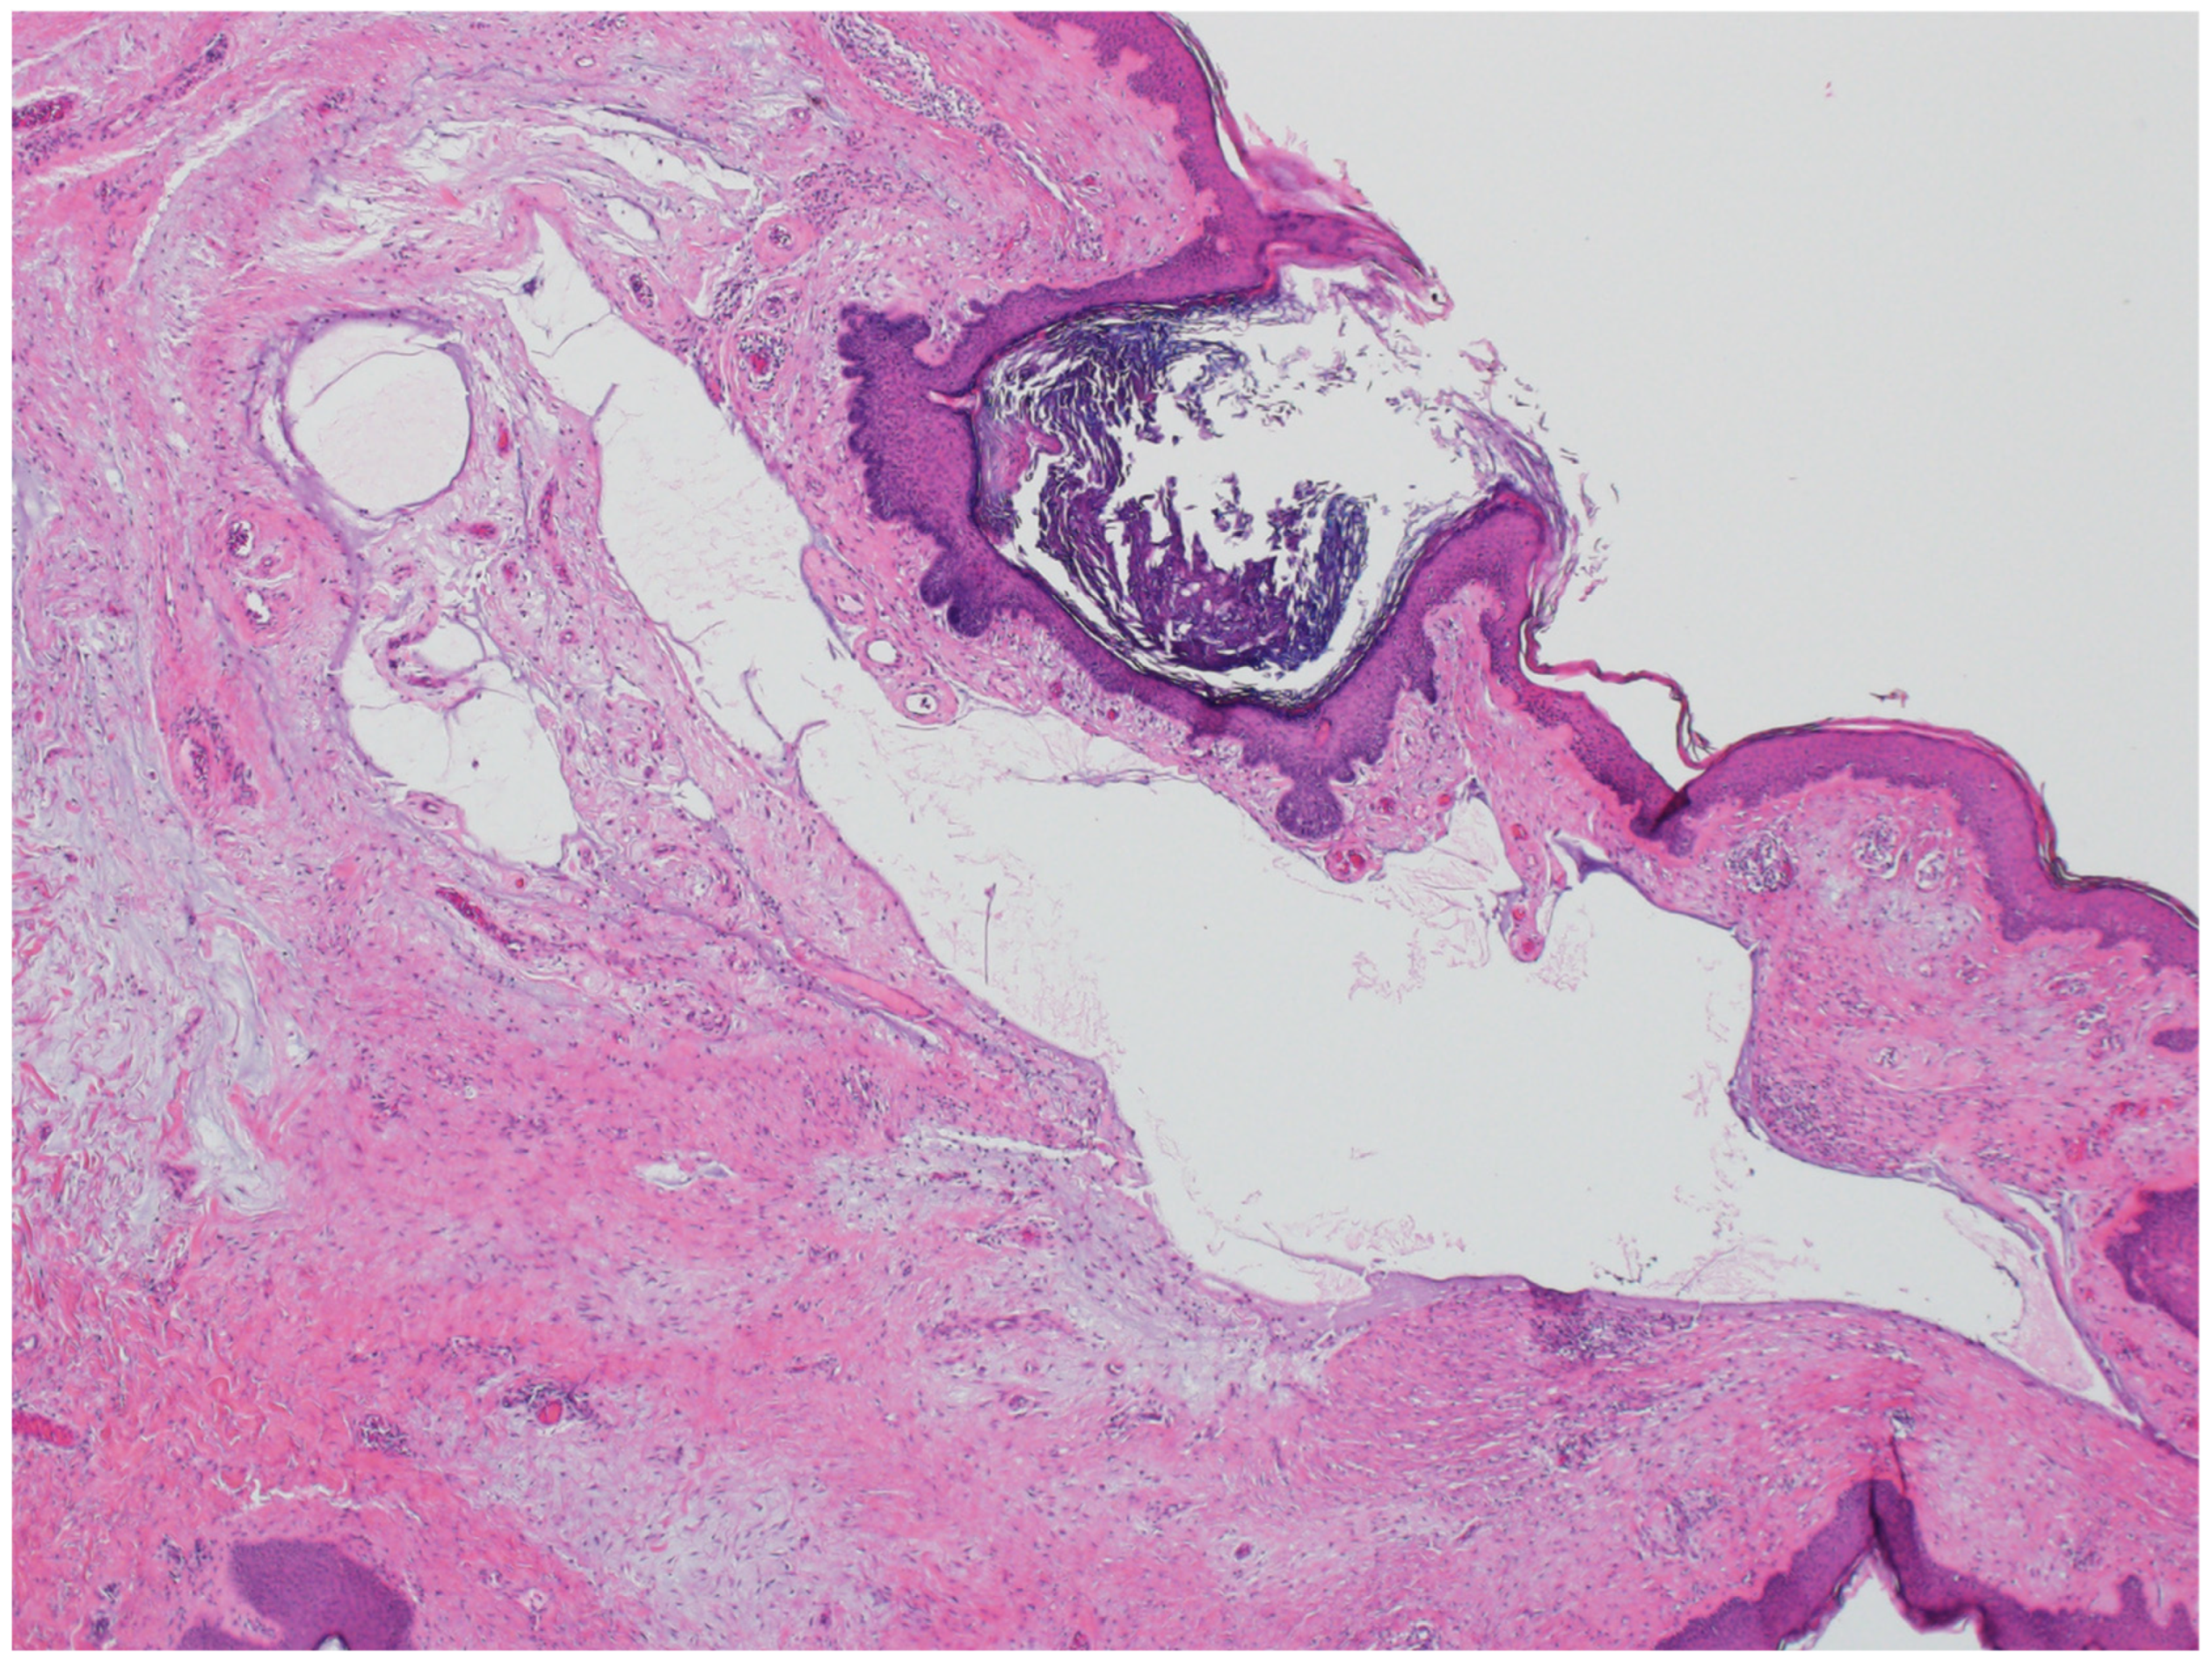

3.2. Steatocystoma